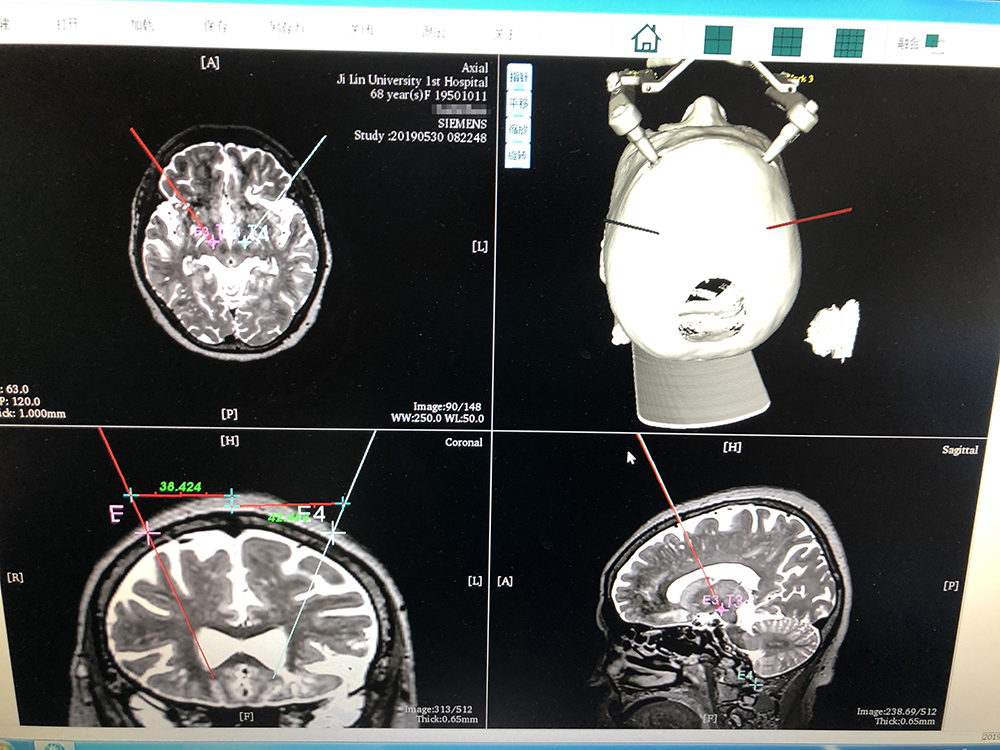

術(shù)前,邱吉慶教授借助“睿米”神經(jīng)外科手術(shù)機(jī)器人配套軟件,為患者制定雙側(cè) STN 核團(tuán)植入電極的手術(shù)路徑規(guī)劃。

借助“睿米”軟件制定手術(shù)規(guī)劃